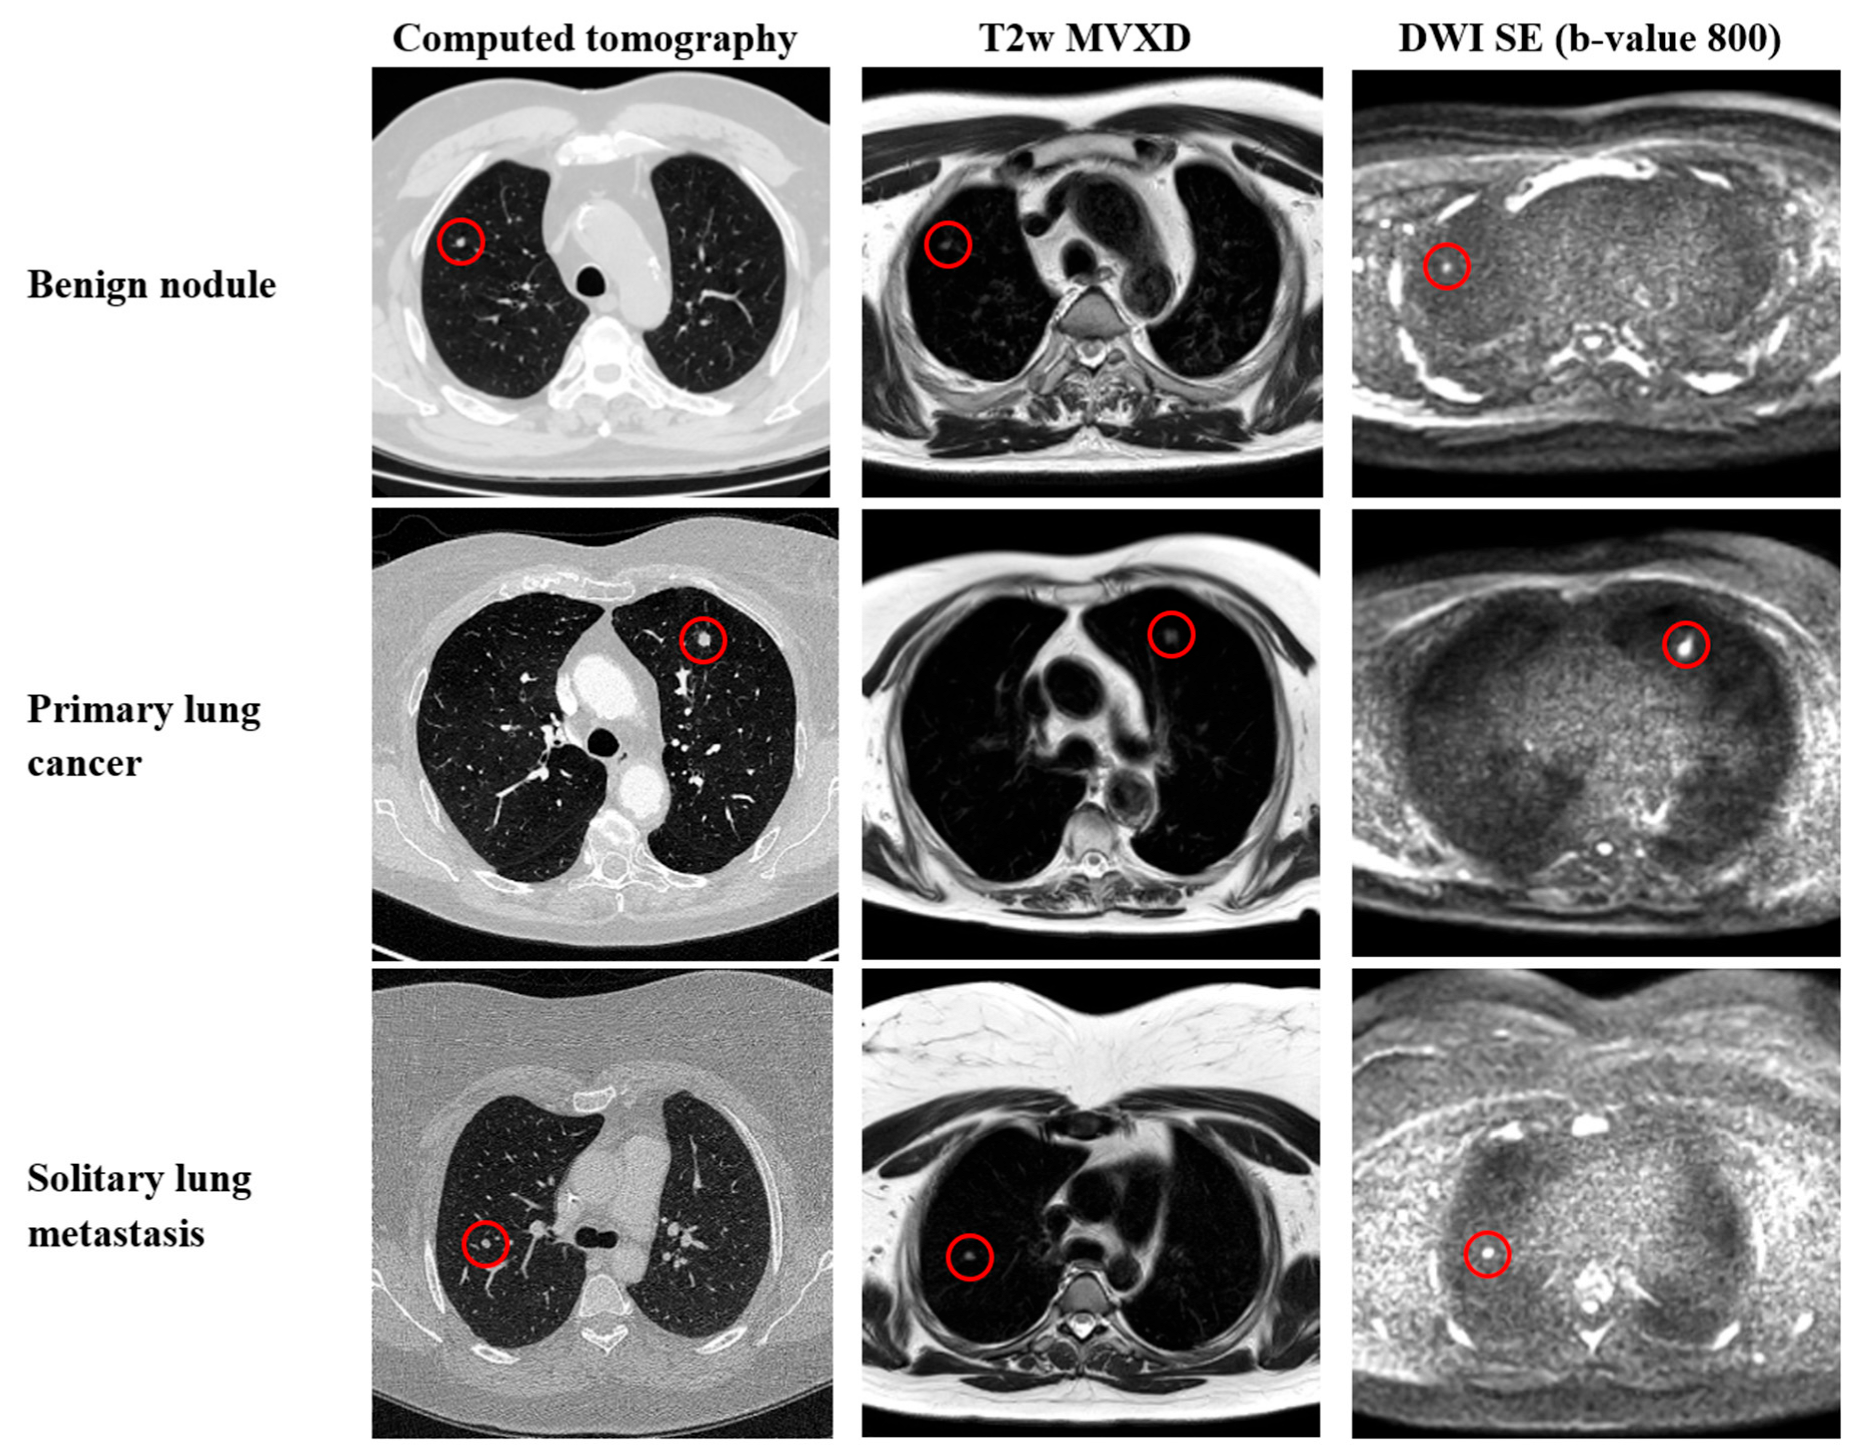

2.2. CT Parameters

2.3. MRI Parameters